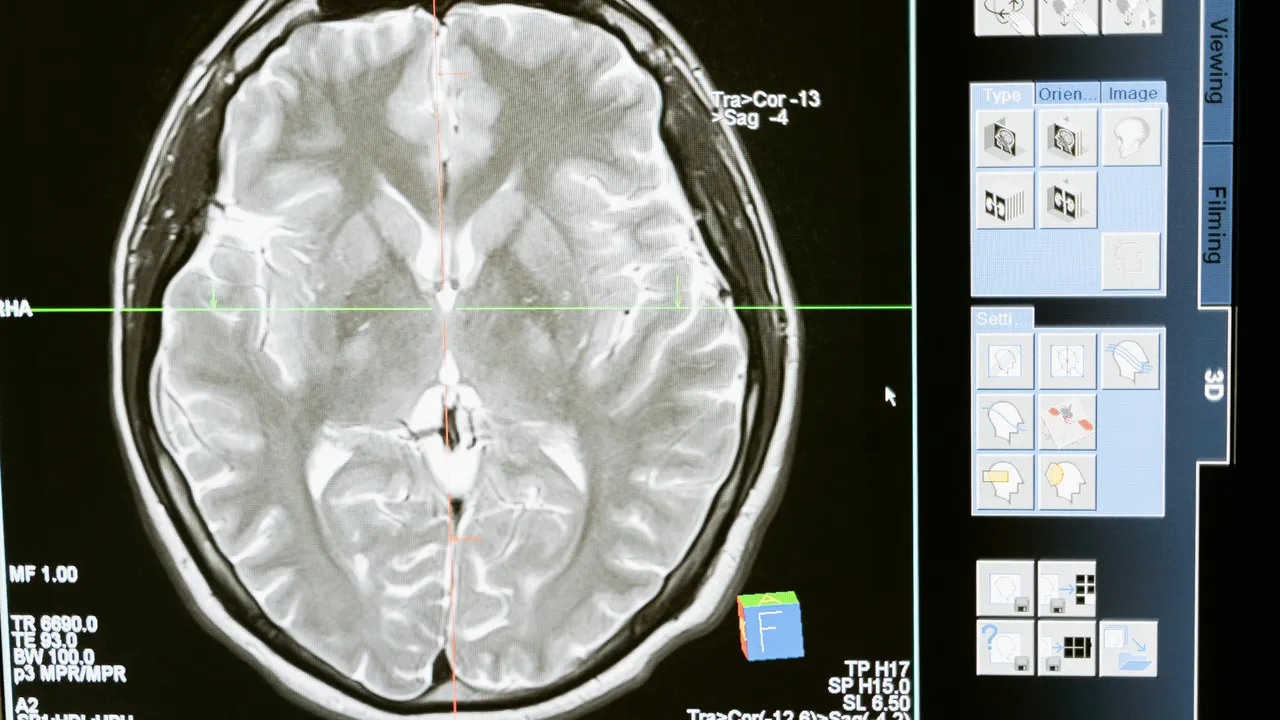

Gelişmiş MRI taramaları ve yapay zeka teknikleri kullanılarak her katılımcının "beyin yaşı" tahmin edildi ve gerçek yaşıyla karşılaştırıldı. Psikolojik ve hayat tarzı faktörlerinin en sağlıklı karışımını bildiren kişilerin beyinleri, beklenenden sekiz yıla kadar daha genç görünüyordu.